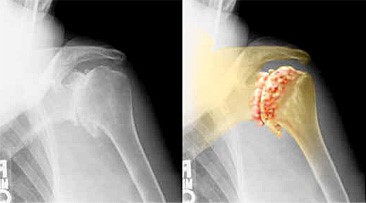

Gewrichtsvlakken zijn bekleed met een dun laagje kraakbeen. Het kraakbeen is een dunne, zachte, en gladde laag dewelke een schok dempende en smerende werking heeft zodat het gewricht optimaal kan bewegen. Bij schouderartrose brokkelt deze kraakbeenlaag af, hetgeen uiteindelijk leidt tot een minder soepele mobiliteit en ‘kraken’ van het gewricht. Het lichaam reageert hierop door zogenoemde ‘osteofyten’ aan te maken: dit zijn papegaaienbek vergroeiingen, vaak duidelijk zichtbaar op conventionele radiografie. Dit geeft uiteindelijk aanleiding tot chronische schouderklachten met verlies van mobiliteit, nachtrust, dagdagelijkse activiteiten en levenskwaliteit.

Meestal volstaat een radiografie. Soms vragen we een artro-mri of een artro-ct aan om de ernst van de artrose beter in kaart te brengen.